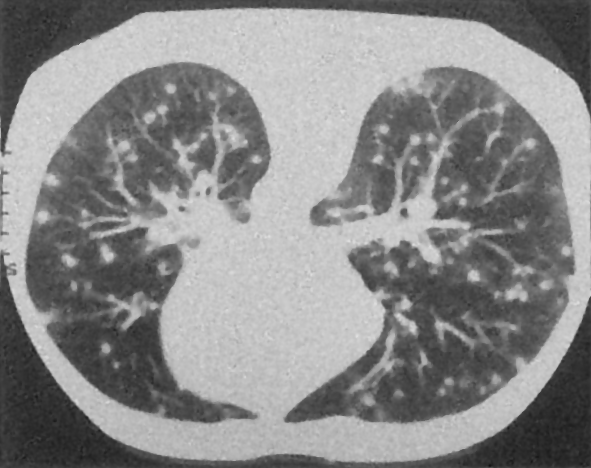

Example 2: restoration of images corrupted by blur and SPN or AWLN. In this example we evaluate the performance of the proposed TV-L1 model on three medical test images lungs (), Fig. 5 (a), ecography (), Fig. 6 (a), and aneurism (), Fig. 7 (a), synthetically corrupted by Gaussian blur of parameters band=5 and sigma=1 and by two types of impulsive noise, namely SPN and AWLN.

In the second part of this example, we consider the restoration of the same three medical test images corrupted by the same blur of parameters

band=5 , sigma=1 and by a different impulsive noise, namely AWLN of level yielding BSNR=10. In Table 2 we report the ISNR values achieved by the compared methods and in Fig. 8 we show the original images, the corrupted images and the restored images by our model.

The results in Table 2 confirm that, also in case of images corrupted by AWLN, the proposed TV-L1 model outperforms

its competitors in terms of ISNR. Moreover, the restored images depicted in the last column of Fig. 8 provide further evidence of the good quality restorations achievable by our proposal.

![]() |

| (a) original | (b) original | (c) original |

| (d) corrupted (BSNR=10) | (e) corrupted (BSNR=10) | (f) corrupted (BSNR=10) |

| (g) TV-L1 | (h) TV-L1 | (i) TV-L1 |

| TV-L1 | TVp-L1 | TV-L1 | TV-L1 | |

|---|---|---|---|---|

| lungs | 6.20 | 6.80 | 7.30 | 7.85 |

| ecography | 5.93 | 6.40 | 7.88 | 8.32 |

| aneurism | 9.10 | 9.44 | 10.13 | 10.70 |